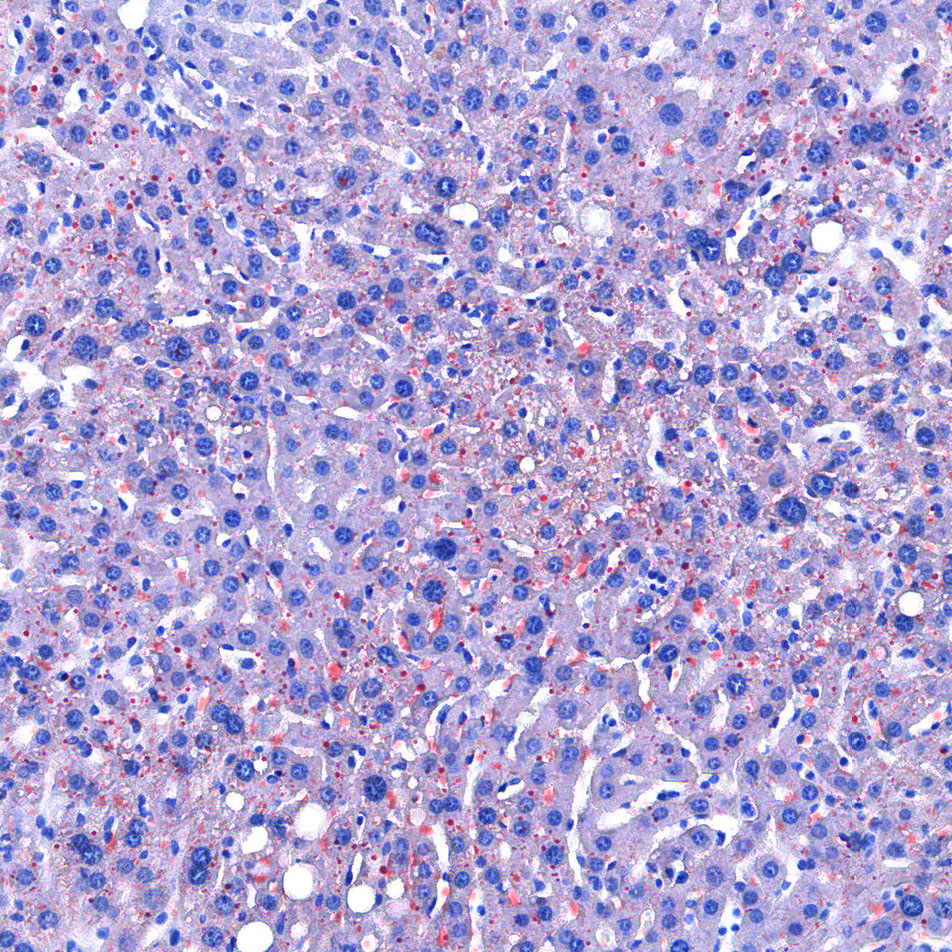

油红O对脂滴的染色机制一般认为是物理学上的溶液作用或吸附作用,借溶液作用使脂质染色,即油红O先溶于60%异丙醇中,然后切片浸入油红O染液中时,油红O在组织脂质的溶解度较60%异丙醇中的溶解度高,所以在染色时油红O从60%异丙醇中转移入脂质中使脂滴显示红色。

实验结果展示:

油红O-肝>